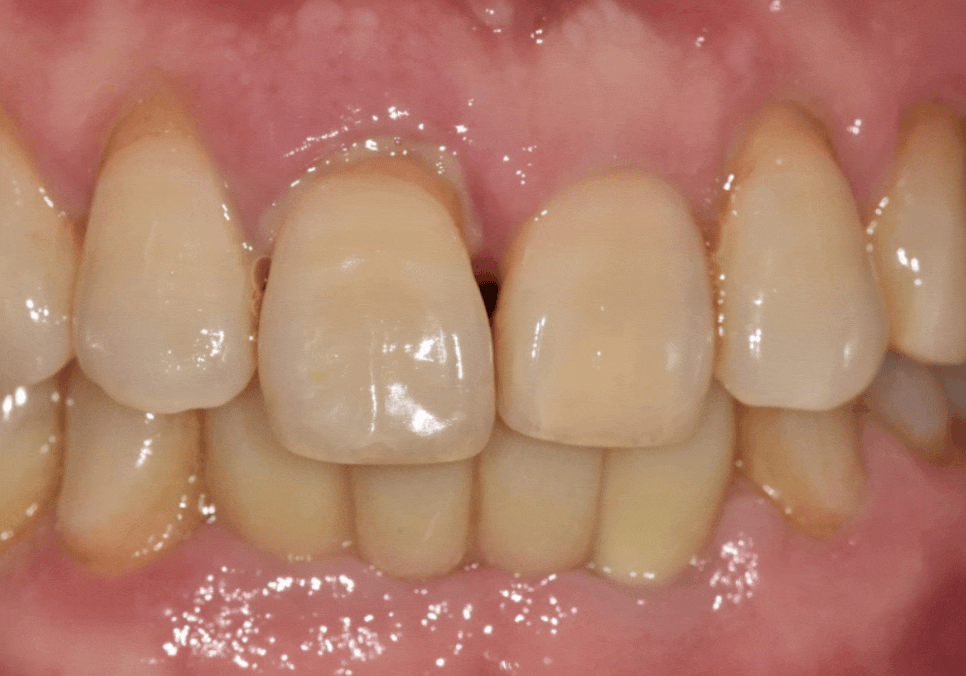

치료 결과

임플란트 식립 후 약 2달간 뼈와 임플란트가

단단하게 한 몸이 되기를 기다렸습니다.

이후 정밀 스캐너로 본을 떠서

주변 치아와 조화를 이루는

최종 보철물을 완성해 드렸어요.

짠! 어떠세요?

전이랑 비교했을 때

확실히 치아가 짧아 보이지 않나요?

옆 치아의 길이와도 대칭을 이뤄

자연스럽게 제작해 드렸답니다!

임플란트 양옆 치아들은

잇몸치료를 꾸준히 한 덕분에

건강한 잇몸까지 되찾을 수 있었습니다.^^